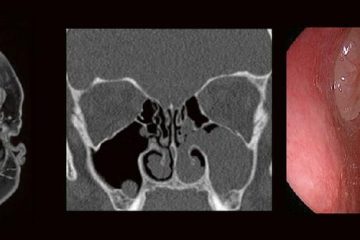

Die technischen Fortschritte bei der Entwicklung neuer Ultraschallgeräte (hochfrequente Ultrabreitband-Linearschallköpfe, Matrixsonden, Verfahren zur Beurteilung der Mikrovaskularisation) sowie Verbesserungen bei der Darstellung von Punktionsnadeln haben in den Gebietender Neurologie, Schmerztherapie, Unfallchirurgie/Orthopädie und Anästhesiologie in den letzten Jahren die Anwendungsbereiche der hochfrequenten Sonographie erheblich erweitert. Unser Anwenderseminar, welches zum 5. Mal ausgerichtet wird, Weiterlesen…